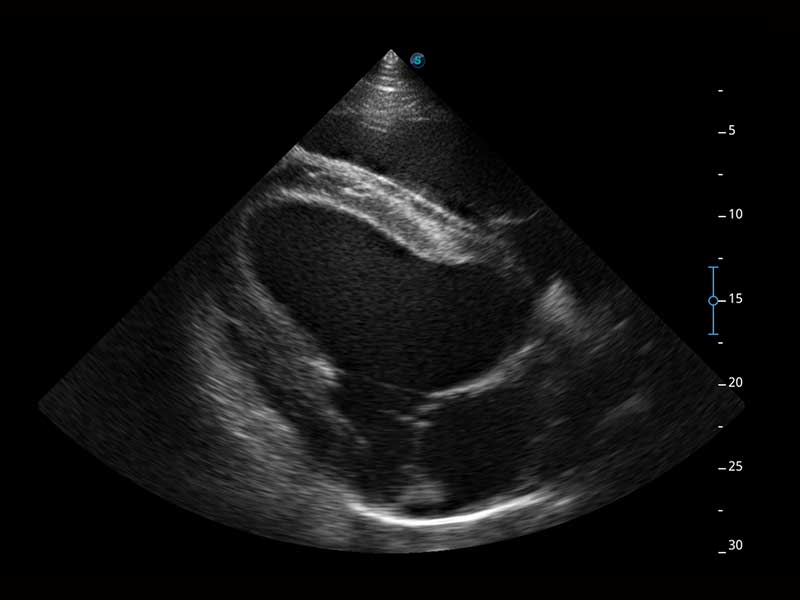

Az X Series Vet platform egy laptop kialakítású színes Doppler ultrahangrendszer, amely kiemelkedő képalkotó technológiáival van felszerelve, és professzionális állatorvosi szoftvereket kínál a kis kedvtelésből tartott állatoktól a nagy haszonállatokig. Kristálytiszta képalkotása és gördülékeny munkafolyamata új, továbbfejlesztett vizsgálati élményt biztosít, amely a magabiztos diagnózishoz szükséges pontosságot nyújtja.

A hatékonyságot, egyszerűséget és sokoldalúságot ötvözve az X Series Vet kiváló választás lógyógyászati vizsgálatokhoz. Speciális transzducerekkel és ló specifikus szoftverekkel felszerelve könnyedén készít lenyűgöző képeket az olyan alapvető alkalmazási területeken, mint az MSK, a reproduktív szervek vizsgálata, valamint a megfelelő penetrációt biztosítja hasi és kardiológiai vizsgálatokhoz is.